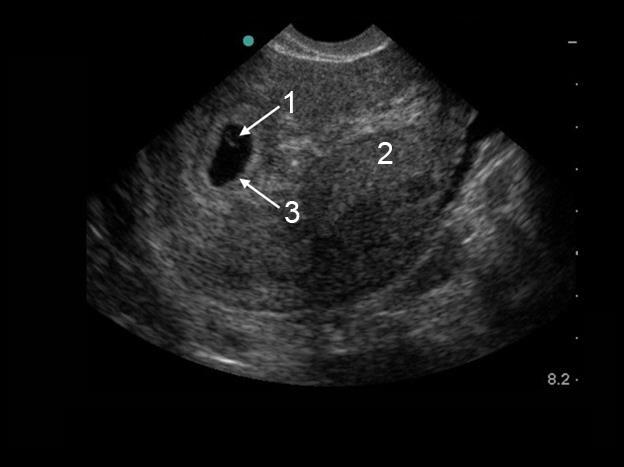

Pelvic Early Gestational Sac with Yolk Sac Image

Yolk Sac

Uterus

Gestational Sac